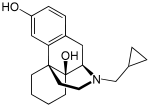

The pharmacodynamic response to an opioid depends upon the receptor to which it binds, its affinity for that receptor, and whether the opioid is an agonist or an antagonist. For example, the supraspinal analgesic properties of the opioid agonist morphine are mediated by activation of the μ1 receptor; respiratory depression and physical dependence by the μ2 receptor; and sedation and spinal analgesia by the κ receptor. Each group of opioid receptors elicits a distinct set of neurological responses, with the receptor subtypes (such as μ1 and μ2 for example) providing even more [measurably] specific responses. Unique to each opioid is its distinct binding affinity to the various classes of opioid receptors (e.g. the μ, κ, and δ opioid receptors are activated at different magnitudes according to the specific receptor binding affinities of the opioid). For example, the opiate alkaloid morphine exhibits high-affinity binding to the μ-opioid receptor, while ketazocine exhibits high affinity to ĸ receptors. It is this combinatorial mechanism that allows for such a wide class of opioids and molecular designs to exist, each with its own unique effect profile. Their individual molecular structure is also responsible for their different duration of action, whereby metabolic breakdown (such as N-dealkylation) is responsible for opioid metabolism.

Several semi-synthetic opioids were developed in Germany in the 1910s. The first, oxymorphone, was synthesized from thebaine, an opioid alkaloid in opium poppies, in 1914.[228] Next, Martin Freund and Edmund Speyer developed oxycodone, also from thebaine, at the University of Frankfurt in 1916.[229] In 1920, hydrocodone was prepared by Carl Mannich and Helene Löwenheim, deriving it from codeine. In 1924, hydromorphone was synthesized by adding hydrogen to morphine. Etorphine was synthesized in 1960, from the oripavine in opium poppy straw. Buprenorphine was discovered in 1972.[228]

- Buprenorphine—partial agonist